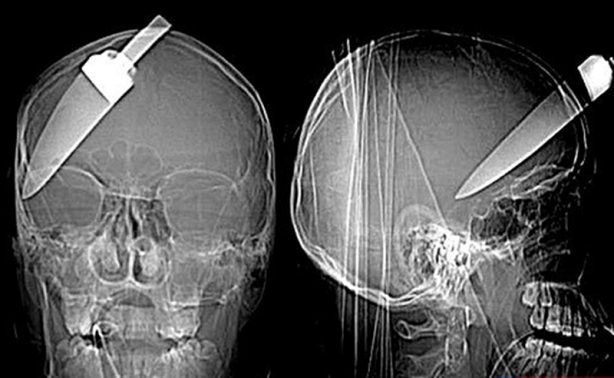

Londra'da başına bıçak saplanan 16 yaşındaki bu çocuk bir mucize eseri kurtuldu.